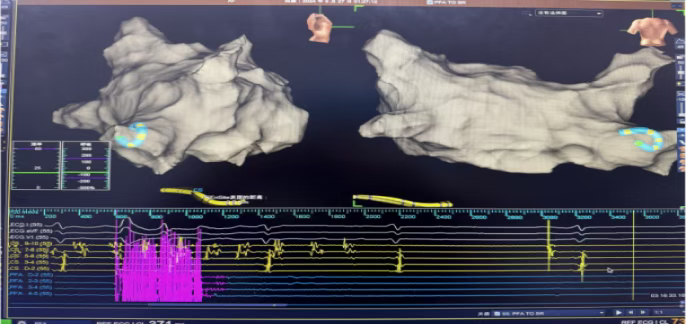

心房颤动脉冲消融

心房颤动消融后转窦图

此次手术中,甘肃省武威肿瘤医院心血管内科团队在学科带头人的带领下,经过详细术前评估与方案研讨,为患者制定了个性化治疗计划。手术全程在三维标测系统引导下进行,医生通过股静脉穿刺将导管送入心脏,精准定位房颤病灶后,启动玄宇RhythPulse®-PFA脉冲消融系统实施消融。整个手术历时仅1.5小时余,术中患者生命体征平稳,术后即刻恢复窦性心律,无任何严重并发症发生。目前患者已顺利康复出院,后续将进行规律随访以监测治疗效果。